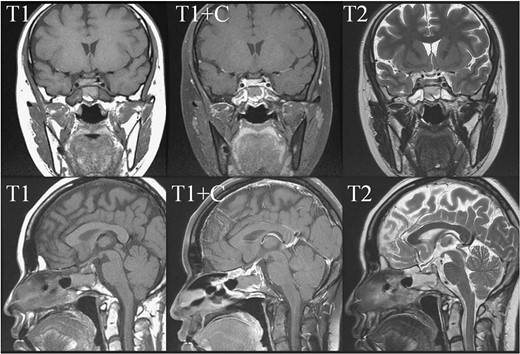

In May 2018, a 28-year-old woman with medical history of sick sinus syndrome and mitral valve prolapse, who just gave birth to a child in April 2018 coming to our Emergency Department with the chief complaint of severe headache and blurred vision for one week. At the Emergency Department, her visual acuity was 0.1 on her right eye and 0.9 on her left eye. Brain CT (computed tomography) scan was checked showing increased soft tissue density over sellar and suprasellar regions, more on the right side. Sellar MRI (magnetic resonance imaging) (Fig. 1) was further arranged which showed a mass with rim enhancement about 2.2 cm ×1.4 cm ×1.2 cm in size located at sella with suprasellar extension with several suspected hemorrhagic foci inside. Under the impression of pituitary apoplexy, she was admitted for further evaluation and management. On admission, her neurological examination showed essentially negative findings except declined right visual acuity; her hormone study showed low level of cortisol (cortisol<1.00 μg/dL) and others were within normal limits. Before surgery, ophthalmologist was consulted again to repeat her ophthalmological examination. The visual acuity of her right eye and left eye improved to 0.8 and 1.0 respectively after the use of steroid. The visual field test showed peripheral defect over the upper visual field of both eyes. Under general anesthesia, she underwent endoscopic endonasal transsphenoidal approach with the removal of tumor and skull base reconstruction. Grossly, the tumor was yellow and soft in consistency and at the end of the procedure, the pituitary gland was well exposed and visible (Fig. 2). After surgery, her vision was subjectively improved; her cortisol level returned to normal (cortisol=16.6ug/dL) and other hormonal data were within normal limits. Histology examination of the tumor (Fig. 3) showed that it composed of spindle to epithelioid cells forming poorly defined lobules and interlacing fascicles, both featuring eosinophilic and oncocytic cytoplasm, with mild nuclear atypia. Immunohistochemically, the neoplastic cells showed TTF-1(+), GFAP(-), EMA(+) Annexin A1(+), and PAS/DPAS(-). Based on the result of histopathology findings and immunohistochemical stains, spindle cell oncocytoma was diagnosed. Before discharge home, her early post-operative sellar MRI (Fig. 4) showed neither residual nor recurrent lesion; she was discharged in a good condition.

Early post-operative sellar MRI. The coronal view (upper row) and sagittal view (lower row) showing the status post removal of the tumor over the sellar and suprasellar regions with poor-enhancing area at the posterior sellar region which favored postoperative change.